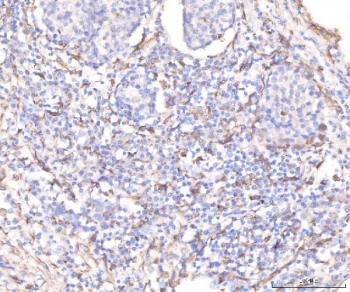

IHC staining of FFPE human breast cancer tissue with KCNQ1 antibody. HIER: boil tissue sections in pH8 EDTA for 20 min and allow to cool before testing.